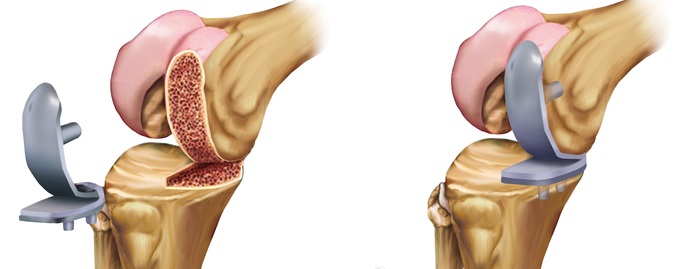

Wie funktioniert der Gelenksersatz?

Erst wird der Schweregrad des Verschleißes ermittelt, woraufhin Art und Größe der Prothese festgelegt werden. Die individuelle Prothese wird dann unter Vollnarkose eingesetzt.